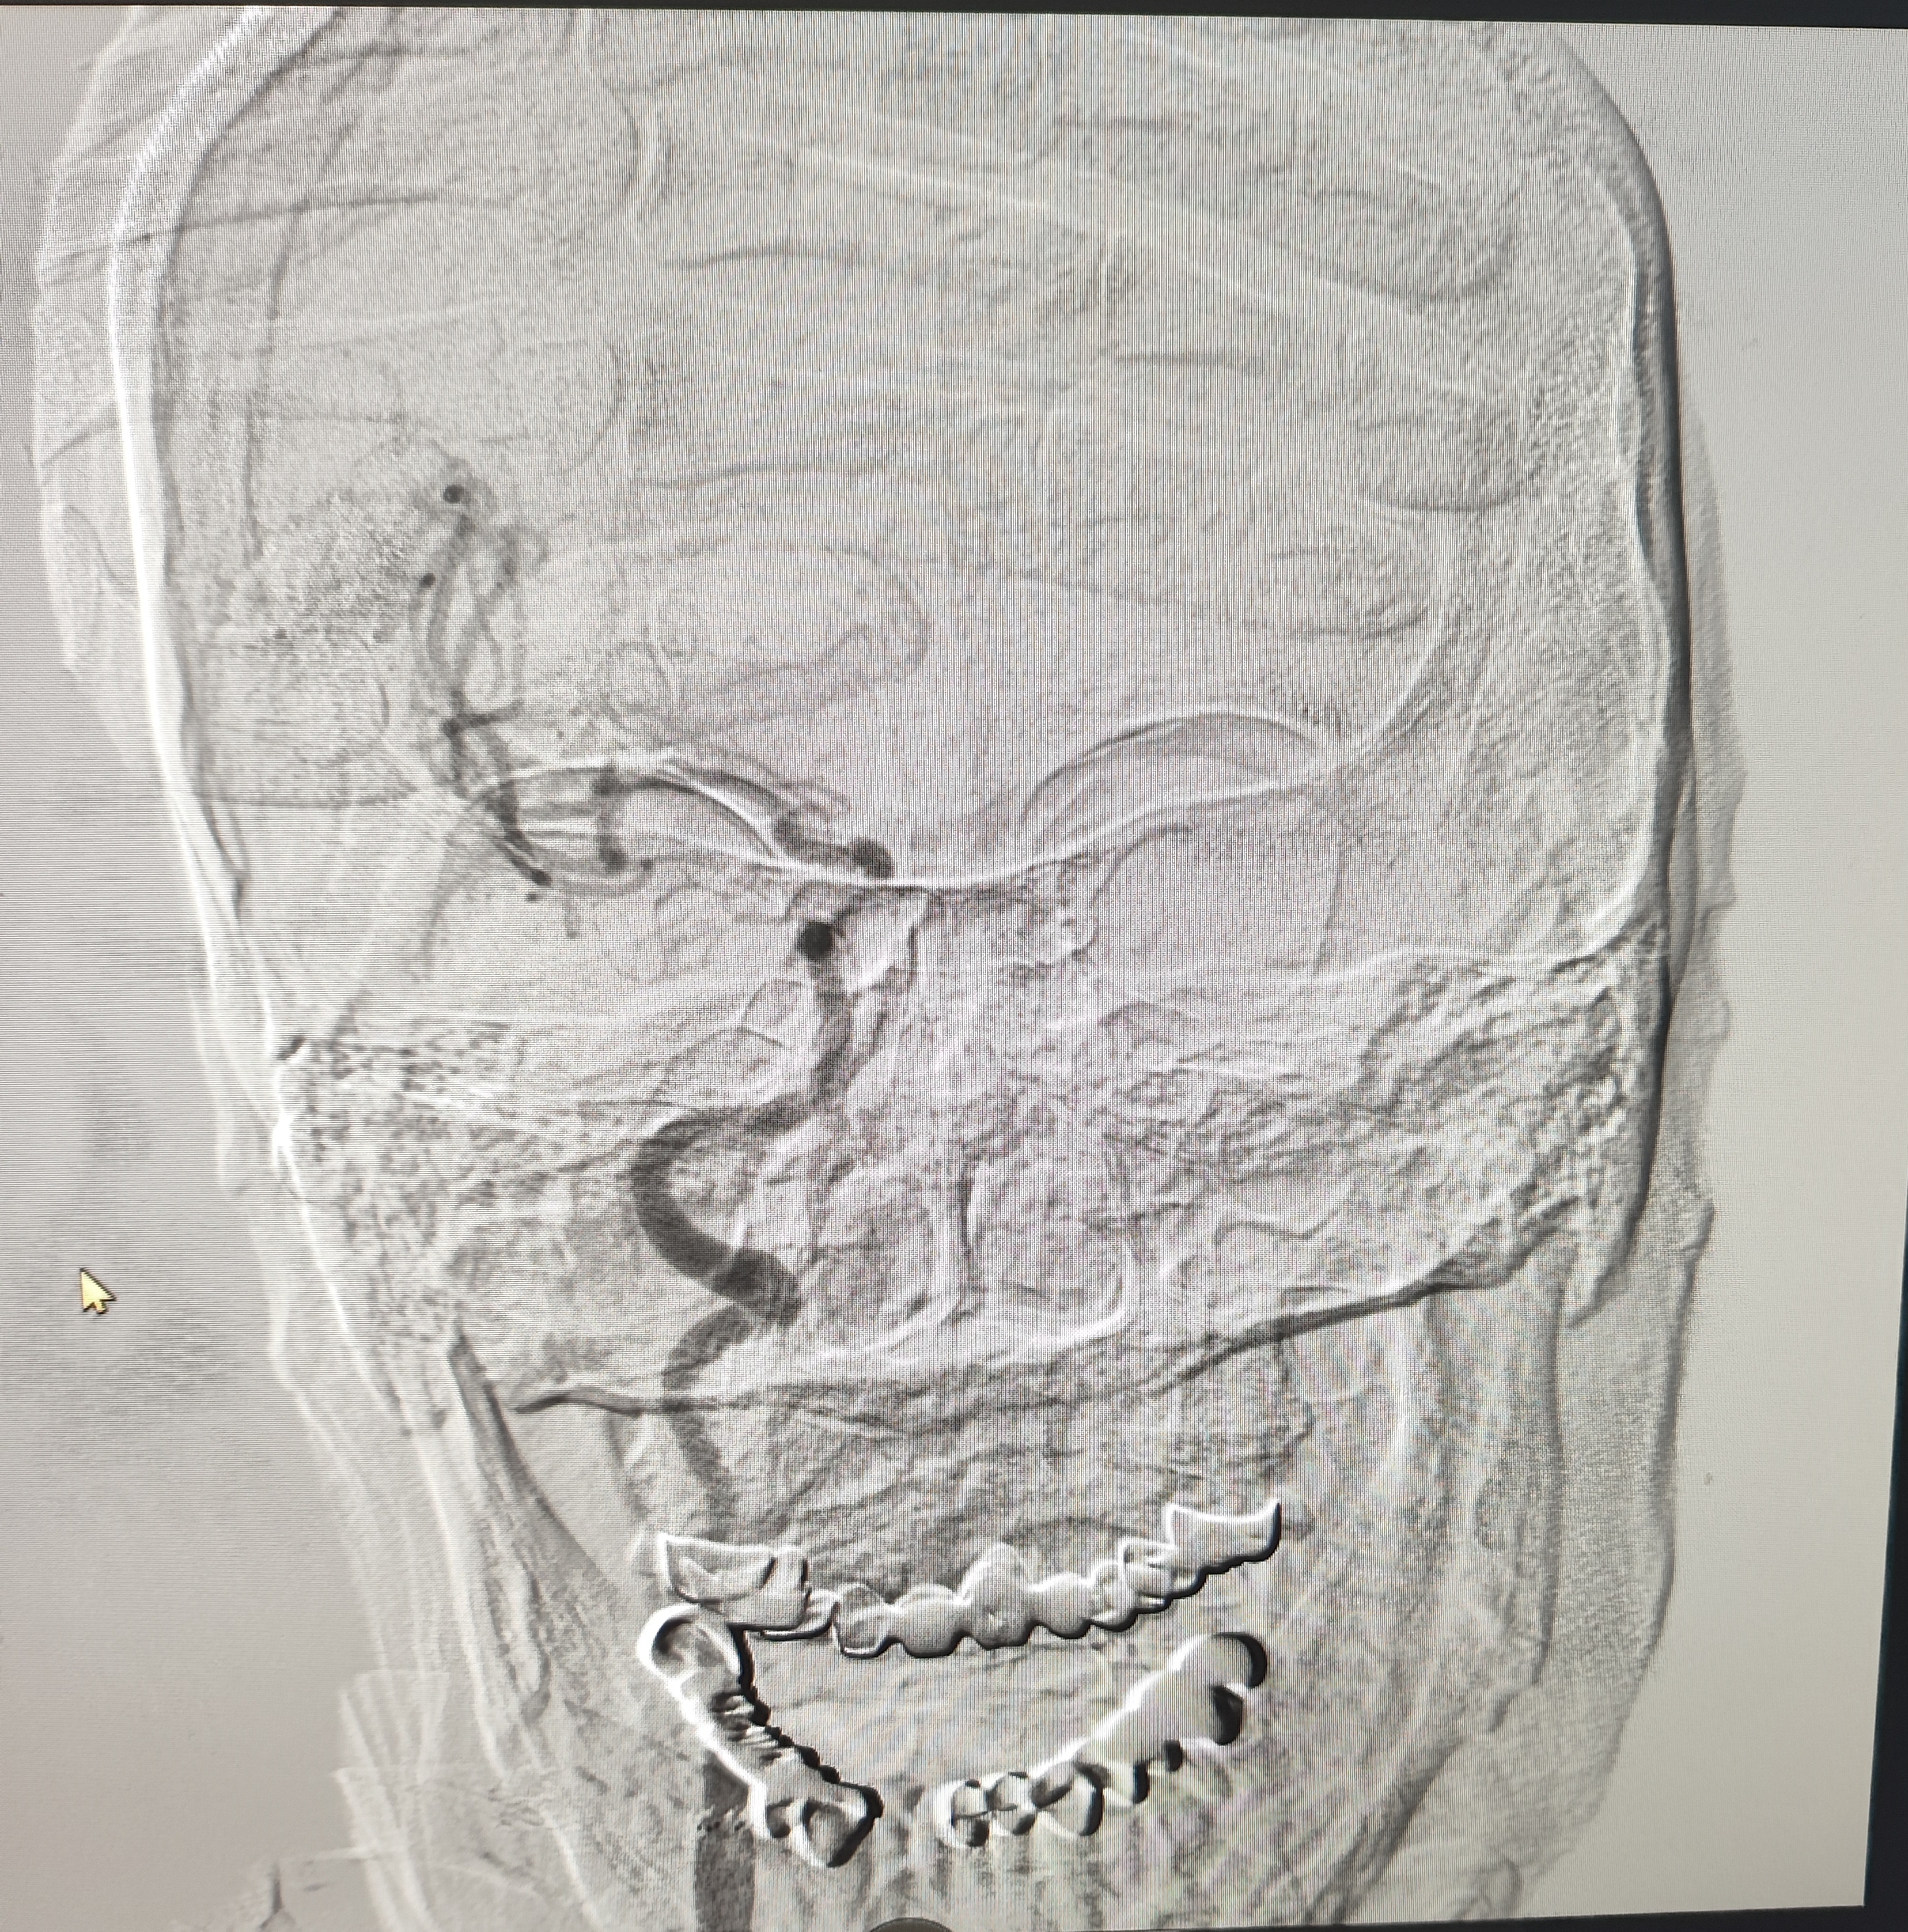

颈总巨大斑块急性闭塞的血管内治疗(双颈动脉支架桥接+支架释放后掉斑块,抽吸取栓)

84岁男性,既往右侧颈动脉狭窄病史8个月,多次脑梗未治疗,本次突发左侧肢体无力来诊,发病30小时后转入我院。

发病当日患者精神差,左侧肢体肌力4级,言语不清晰,左侧鼻唇沟略浅。

症状进行性加重,意识逐渐模糊,烦躁,左上肢肌力1级,左下肢肌力2级,当地考虑开通难度大,转入我院。

急诊上台。